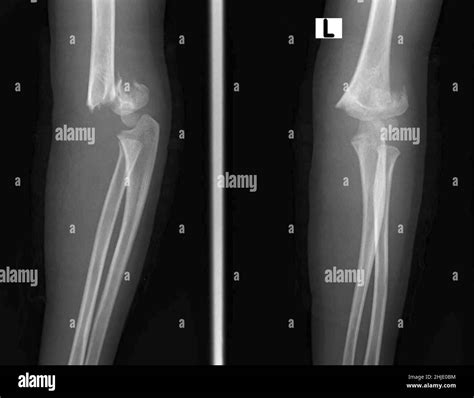

Diagnosing Supracondylar Humerus Fractures

Diagnosing a supracondylar humerus fracture involves a thorough physical examination and imaging studies. The healthcare provider will assess the elbow for signs of injury, such as swelling, deformity, and tenderness. Imaging studies, such as X-rays, are crucial for confirming the diagnosis and determining the type and severity of the fracture.

X-rays are typically taken from multiple angles to provide a comprehensive view of the fracture. In some cases, additional imaging studies, such as a CT scan or MRI, may be necessary to assess the extent of the injury and plan the appropriate treatment.

Supracondylar humerus fractures are classified based on the direction of the fracture line and the displacement of the bone fragments. The most commonly used classification system is the Gartland classification, which includes three types:

Type II Displaced fracture with posterior angulation of the distal fragment

Type III Completely displaced fracture with no cortical contact between the fragments